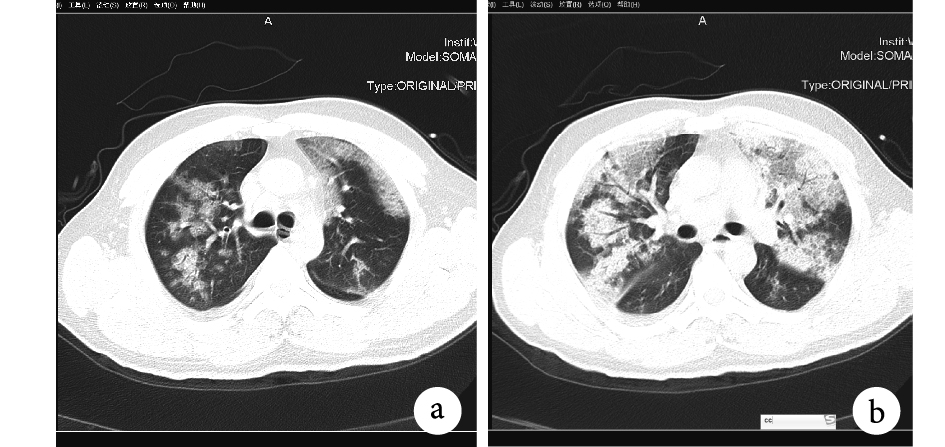

a. 雙肺散在斑片影;b. 雙肺散在磨玻璃及實變影

病例介紹 患者,男,42 歲。因“呼吸困難,伴咳嗽、發熱,體溫最高 41℃”于 2016 年 1 月 3 日入住我院急診科。2015 年 12 月 28 日患者無明顯誘因出現畏寒、寒戰、發熱,體溫最高 39℃,遂就診于當地醫院,經過對癥、支持治療后癥狀無改善。2016 年 1 月 1 日,患者出現咳嗽癥狀,咳黃色濃痰,在當地醫院行胸部 CT 檢查示右肺肺炎。入住我院后行 CT 檢查結果示:雙肺散在斑片影、磨玻璃及實變影(圖 1);實驗室檢查結果顯示:流感病毒抗原為陰性,給予氣管插管、抗炎、補液等治療后于 1 月 4 日收入重癥監護病房(Intensive Care Unit,ICU),入科診斷為“重癥肺炎,呼吸衰竭”。因為病因不明,收至單人病房,同時醫務人員做好標準職業防護。入 ICU 后給予呼吸支持、鎮痛鎮靜,予抗炎、體外膜肺氧合、連續腎臟替代療法、祛痰、抑酸等對癥和支持治療,同時積極搜尋病因,實驗室結果顯示尿軍團菌抗原陰性,血培養陰性,骨髓細菌培養陰性,肺組織及痰培養陰性。因患者發病原因不明,病程進展迅速而常規各項檢查都未能尋找出致病因素,此后,進行呼吸道 13 種病毒檢測,1 月 11 日病毒檢測結果示:甲型流感病毒陽性。確診后立即上報醫院感染管理科(院感科),院感科隨即通知所屬區域疾病控制中心留取標本進一步鑒定亞型。1 月 13 日亞型鑒定結果為 H5N1 高致病性禽流感,科室采取了全方位精細化的感染控制措施,積極應對,在做好相應隔離措施的同時繼續對癥支持治療,積極維持患者各器官功能。雖積極進行搶救,但患者因病情危重,于 2 月 16 日搶救無效死亡。在患者入住 ICU 的 43 d 及后續觀察期內,所有密切接觸過患者的醫務人員(包括醫生 12 名、護士 20 名、工人 4 名,共 36 人),均無禽流感疫情報告;經回訪急診科接診醫務人員也無疫情報告。患者所產生的醫療廢物都得到規范化、妥善處理,未發生患者所接觸過物品與正常患者所使用物品的混合,疫情無擴散。